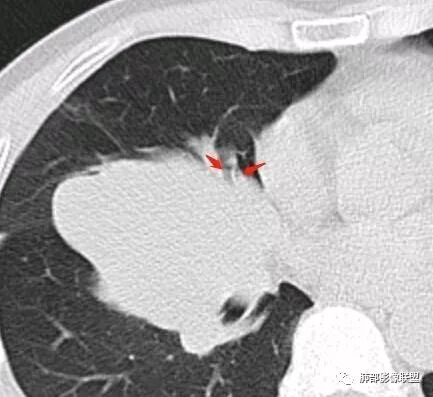

崇军:右侧中叶支气管与下叶支气管夹角处的肿块,支气管没有堵塞仅仅推移,不是支气管来源,纵隔来源也可以排除;跨叶,边界清,平扫无明显坏死,来源只剩下淋巴,血管与胸膜,如果是淋巴,纵隔未见其他淋巴结,淋巴瘤排除,巨淋巴增生症可能,血管来源,PSP可能,胸膜来源,SFT可能,这三者没有增强难鉴别。张帅:病灶边缘光滑,气管挤压呈贴边征,赞同王崇军老师观点:增大淋巴结,但同时需鉴别PSP及类癌。

南边:这类片其实很艰难Shelia:应该有个增强崇军:是的,如果没有老师您以前的讲述,一个肺门占位就发出去了风儿:肿块跨叶生长,边缘光滑,有膨隆有平直,支气管血管受压,病灶后方支气管似乎进入病灶后堵塞,与纵隔胸膜呈锐角,来源肺内-神经内分泌肿瘤?胸膜-SFT?血管-PSP?临近心包少量积液右侧胸腔少量积液是否与肿块有关

这一个类圆形,边界光滑,明显膨胀生长为主,如果起源中叶支气管,按理中叶支气管不动,固定在中叶支气管上,推移其他结构

但是现在的片显示,其主体在下叶,中叶支气管壁由下朝上有推移

南边:就不符合这个原理

南边:病灶边界清,提示侵袭性弱,膨胀生长为主;这时候我们提示病灶不应该是支气管关系密切,提示间叶来源或胸膜来源